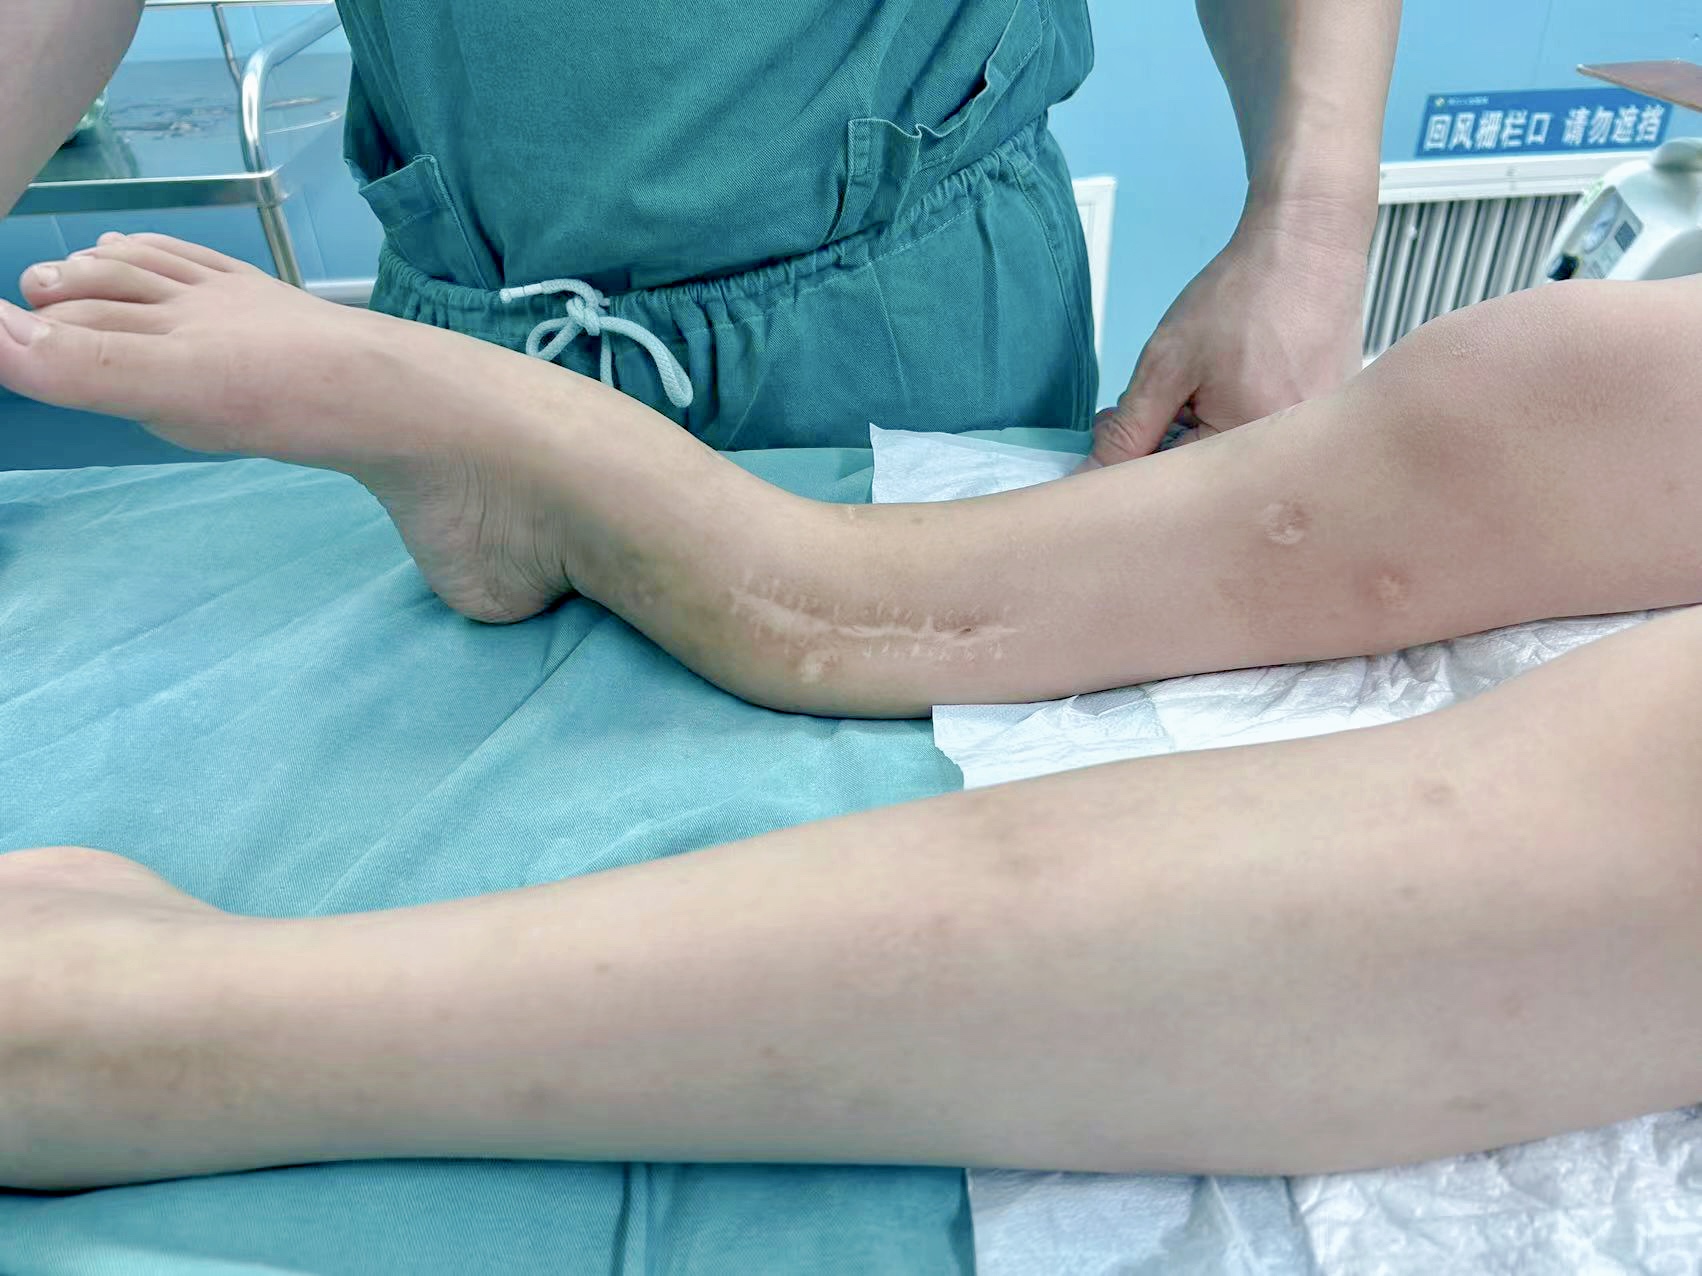

▲术前

对于“成骨不全症”(俗称“脆骨病”)患者而言,人生每一步都充满挑战。一位自幼年被此病困扰的少年,其右小腿自2岁起便历经多次骨折与手术,虽经多次治疗,却仍留下了肢体短缩、向前成角的严重畸形。今年,畸形进一步加重,功能严重受限,他与家人怀着最后的希望,再次走进了他们最信赖的周口人合医院骨三科。